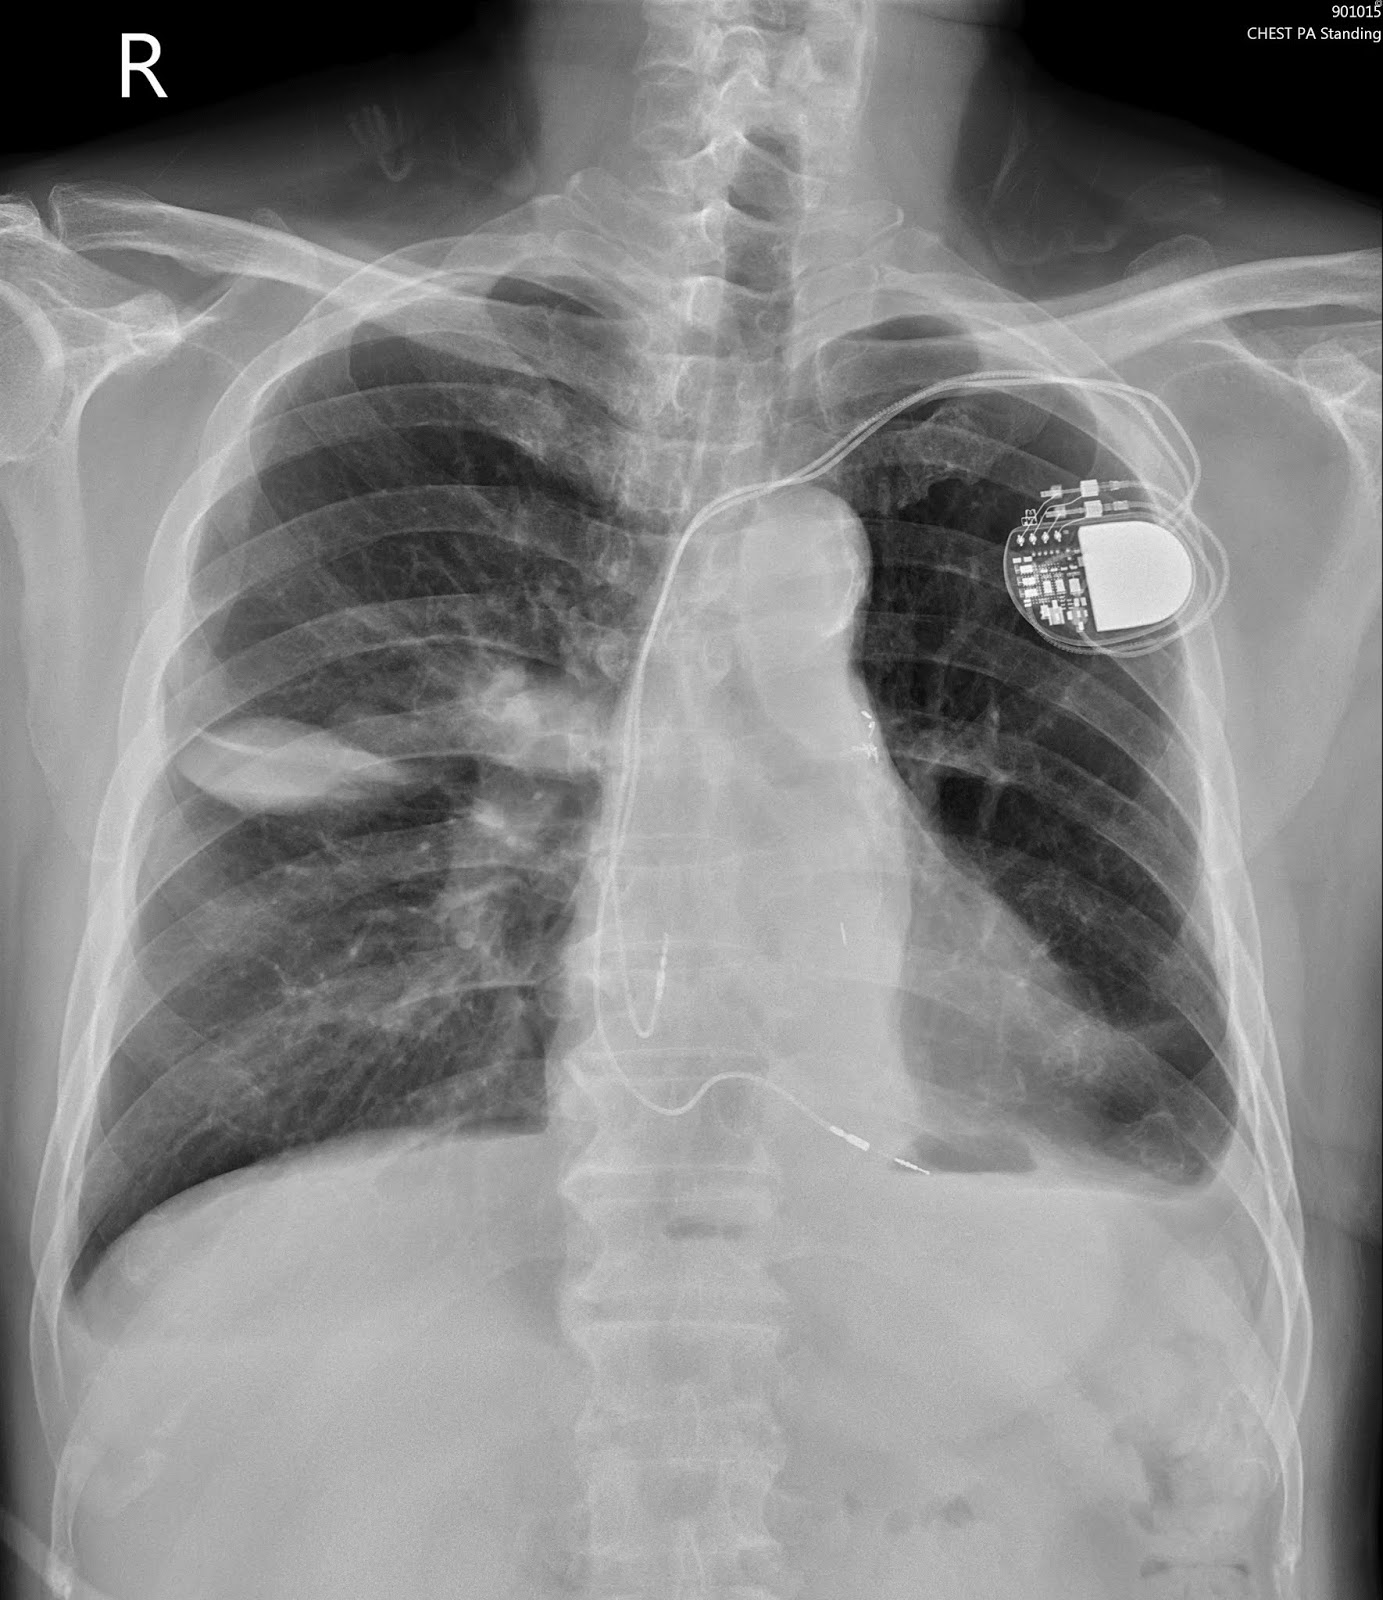

A pleural effusion is accumulation of excessive fluid in the pleural space, the potential space that surrounds each lung. Case contributed by dr prashant mudgal. Pleural effusions occur as a result of increased fluid formation and/or reduced fluid resorption. Pleural fluid ldh > two thirds of upper limit for serum ldh. Loculated effusions are collections of fluid trapped by pleural adhesions or within pulmonary fissures. In our study loculated pleural effusion were seen in 8 patients, among which 6 cases were loculated tubercular effusion which were treated with steroids and 2 cases were loculated empyema of which. Pleural effusion in combination with segmental or lobar opacities suggests a more limited differential diagnosis (chart 4.3). Pleural effusion with segmental and lobar opacities. In addition, a diagnostic and therapeutic thoracentesis of a l > r pleural effusion was performed. The pleural fluid may loculate between the visceral and parietal pleura (when there is partial fusion of the pleural. Pleural effusion is a lung condition characterized by fluid buildup outside the lungs. Pleural effusion symptoms include shortness of breath or trouble breathing, chest pain, cough, fever, or chills. Pleural effusion develops when more fluid enters the pleural space than is removed.

The pleura are thin membranes that line the lungs and the. .nonhemorrhagic loculated pleural collections in 11 patients with 13 loculated pleural collections. Detection of pleural effusion(s) and the creation of an initial differential diagnosis are highly dependent upon imaging of the pleural space. Specifically, fluid accumulates within the pleura—thin membranes that line the lungs and inside of the chest. Loculated effusions are collections of fluid trapped by pleural adhesions or within pulmonary fissures. Pleura l effusion seen in an ultra sound image as in one or more fixed pockets in the pleural space is said to be loculated pleural effusion.in. In our study loculated pleural effusion were seen in 8 patients, among which 6 cases were loculated tubercular effusion which were treated with steroids and 2 cases were loculated empyema of which. Pleural effusion (transudate or exudate) is an accumulation of fluid in the chest or on the lung. Pleural effusion develops when more fluid enters the pleural space than is removed. Pleural infection pleural inflammation pleural malignancy (most often pleural fluid analysis findings: In transudative effusion, specific gravity is below 1.015 and. Pleural fluid ldh > two thirds of upper limit for serum ldh. Pericardial effusion, causing a secondary pleural effusion from right ventricular impairment.

Chest roentgenogram. Plain chest film showed right-side ... from www.researchgate.net Pleural effusion is classically divided into transudate and exudate based on the light criteria. Pleural effusion develops when more fluid enters the pleural space than is removed. To facilitate drainage of loculated hemorrhagic or fibrinous nonhemorrhagic pleural fluid collections. In transudative effusion, specific gravity is below 1.015 and. Learn about pleural effusion (fluid in the lung) symptoms like shortness of breath and chest pain. Pleural effusions occur as a result of increased fluid formation and/or reduced fluid resorption. Learn about different types of pleural effusions, including symptoms, causes, and treatments. Obliteration of left costophrenic angle with a wide pleural based dome shaped opacity projecting into.

A pleural effusion is accumulation of excessive fluid in the pleural space, the potential space that surrounds each lung. Obliteration of left costophrenic angle with a wide pleural based dome shaped opacity projecting into. Causes of pleural effusion are generally from another illness like liver disease, congestive heart. Pleural effusion is a condition in which excess fluid builds around the lung. Pleural effusion with segmental and lobar opacities. Pleural fluid/serum ldh ratio >0.6. In transudative effusion, specific gravity is below 1.015 and. Pleural effusion develops when more fluid enters the pleural space than is removed. Learn about pleural effusion including causes of pleural effusion. Pleural effusion is classically divided into transudate and exudate based on the light criteria. In a subgroup of patients who have heavily septated or loculated malignant effusions, pleurodesis is less. Case contributed by dr prashant mudgal. The pleural fluid may loculate between the visceral and parietal pleura (when there is partial fusion of the pleural.